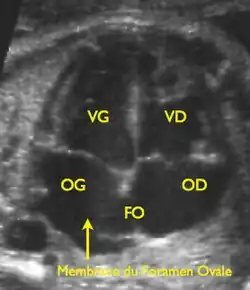

Le foramen ovale est un passage en forme de fente « en chicane » entre les deux constituants principaux de la cloison inter-auriculaire, le septum primum du côté gauche et le septum secundum du côté droit. Il fait communiquer les deux atriums. Il tend à être fermé par une membrane (« la membrane du foramen ovale ») qui n'est maintenue en position ouverte que par la différence de pression régnant dans les atriums.

Cœur fœtal.

La circulation pulmonaire du nouveau-né devient parfaitement fonctionnelle et assure 100 % du débit cardiaque (contre 7 % seulement avant la naissance). Le retour de cette circulation pulmonaire, par les veines pulmonaires qui s'abouchent dans l'atrium gauche, provoque une élévation des pressions régnant dans cette cavité, lesquelles finissent par dépasser celles de l'atrium droit. La membrane du foramen ovale tend alors à être plaquée contre la cloison interauriculaire et à interdire tout passage significatif de sang par cette communication.